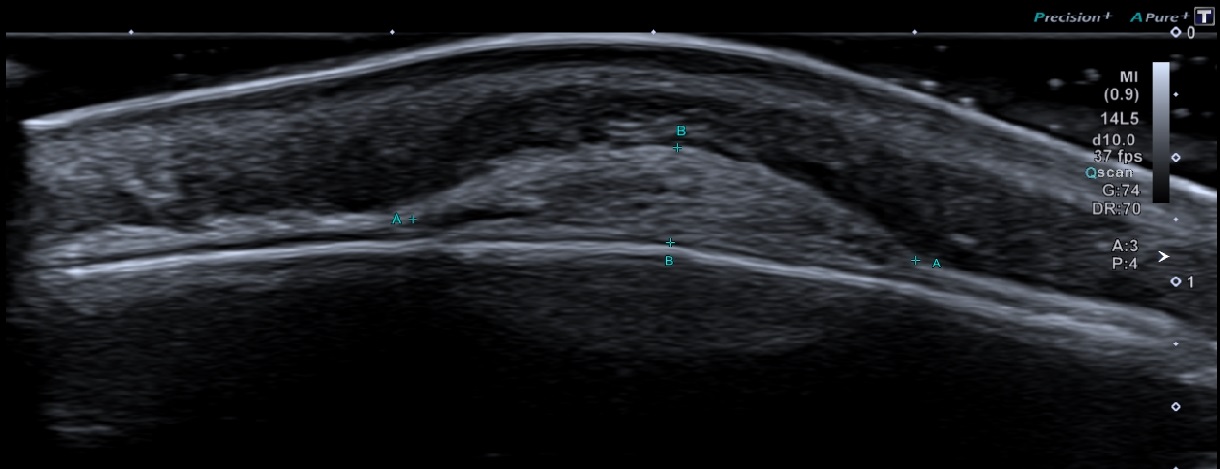

Forehead lump, mobile, soft and fluctuant, persistent for more than 1 year.

Solid echogenic mass between the periosteum and galea aponeurosis. It has a relatively flat base and smooth convex displacement of galea aponeurosis. No vascularity. Underlying bony cortex is smooth.

Subgaleal lipoma.